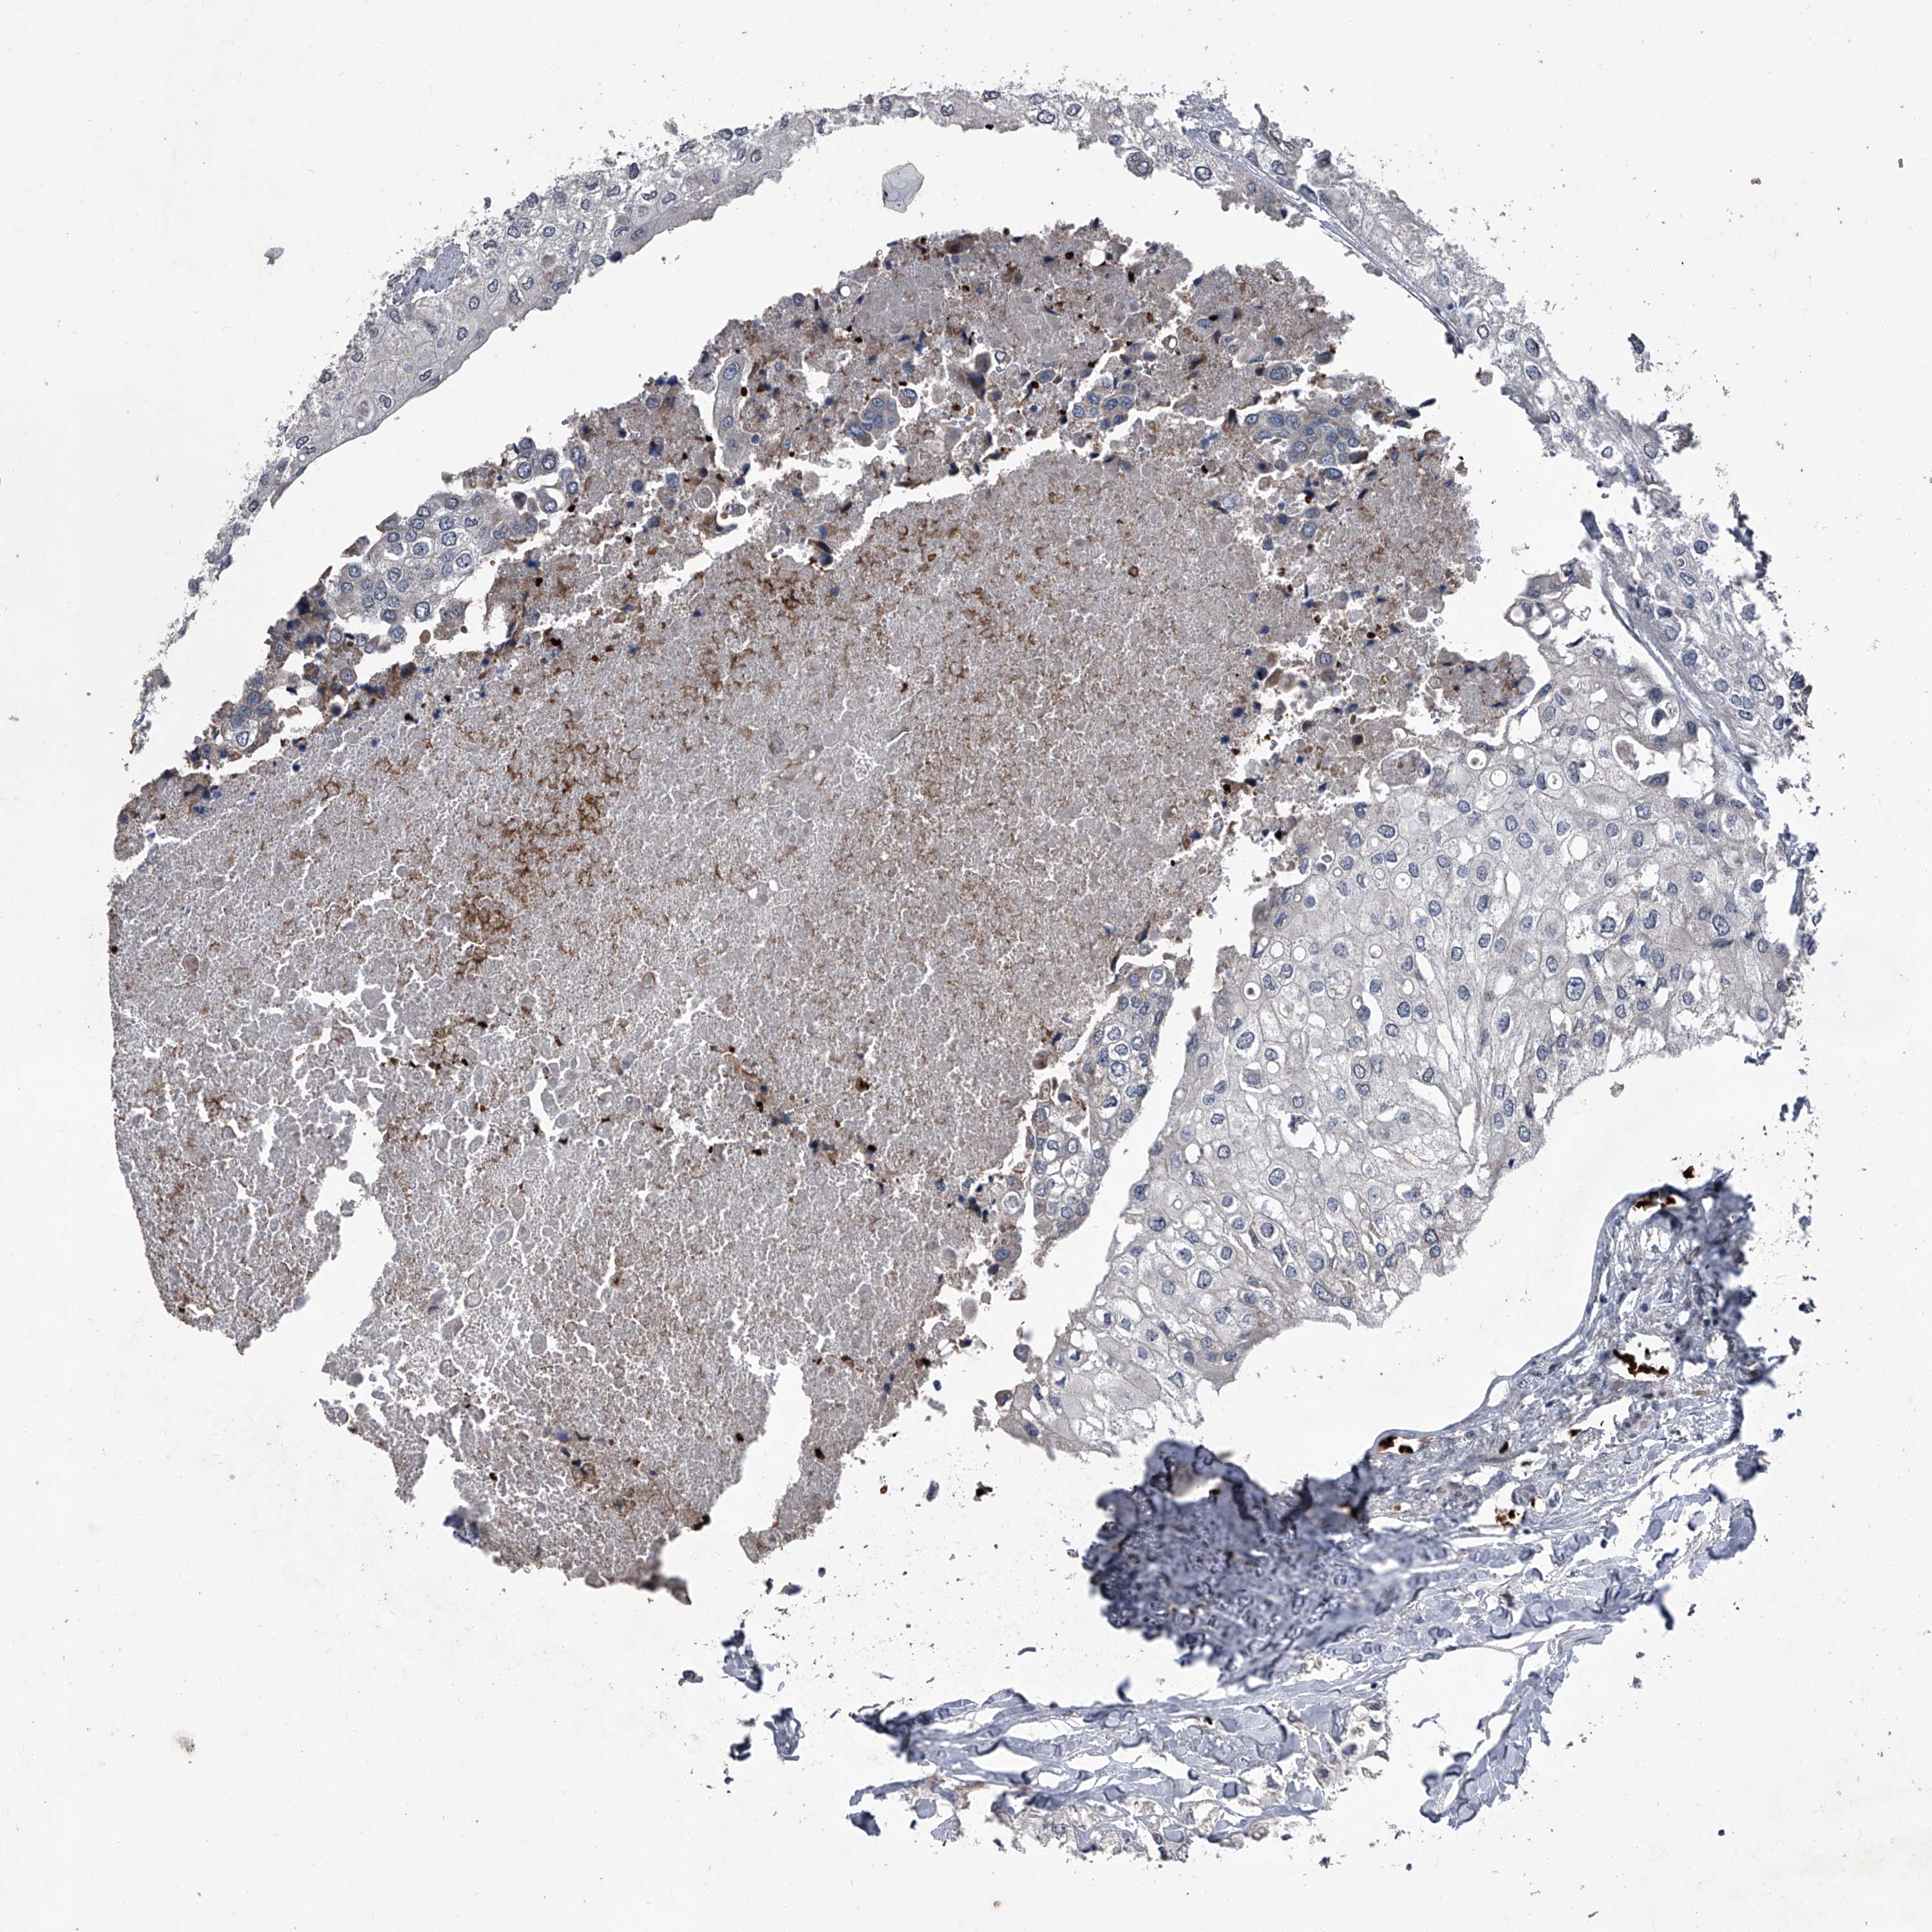

UROTHELIAL CANCER - Protein expressioni

A mouse-over function shows sample information and annotation data. Click on an image to view it in a full screen mode. Samples can be filtered based on level of antibody staining by selecting one or several of the following categories: high, medium, low and not detected. The assay and annotation is described here.

Note that samples used for immunohistochemistry by the Human Protein Atlas do not correspond to samples in the TCGA dataset.

Antibody stainingi

Antibody staining in the annotated cell types in the current human tissue is reported as not detected, low, medium, or high, based on conventional immunohistochemistry profiling in selected tissues. This score is based on the combination of the staining intensity and fraction of stained cells.

Each image is clickable and will lead to virtual microscopy that enables deeper exploration of all samples and also displays staining intensity scores, fraction scores and subcellular localization as well as patient and tissue information for each sample.

Antibody HPA029137

Antibody HPA029138

Antibody HPA029139

Staining

High

Medium

Low

Not detected

Intensity

Strong

Moderate

Weak

Negative

Quantity

>75%

75%-25%

<25%

None

Location

Nuclear

Cytoplasmic/membranous

Cytoplasmic/membranous,nuclear

Urothelial carcinoma, Low grade

Urothelial carcinoma, High grade